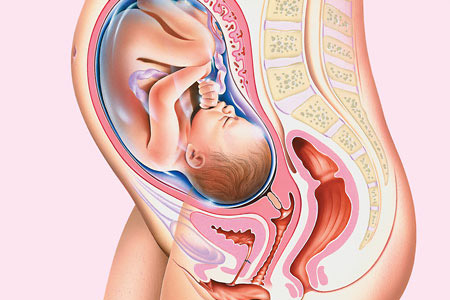

Guida gravidanza: ottavo mese

Per la Guida gravidanza oggi parleremo dell’ottavo mese di gravidanza è quello che va da 30+5 a 35+0 settimane; è in questo mese che il piccolo decide come nascere.

OTTAVO MESE: COSA FARE

Nell’ottavo mese di gravidanza si chiede il congedo di maternità, ossia l’astensione dal lavoro (il congedo continuerà poi anche nei 2 mesi dopo la nascita del piccolo); per maggiori informazioni e per approfondire questo argomento potete consultare il sito dell’Inps.